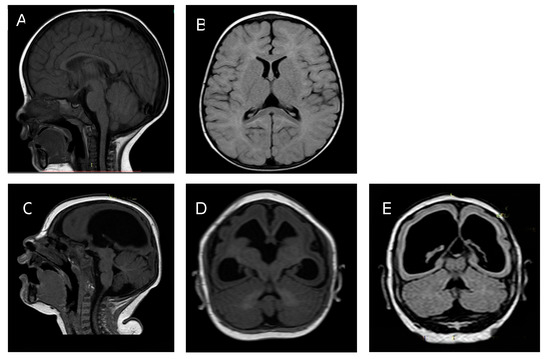

3.2.1. Twin A

3.2.2. Twin B